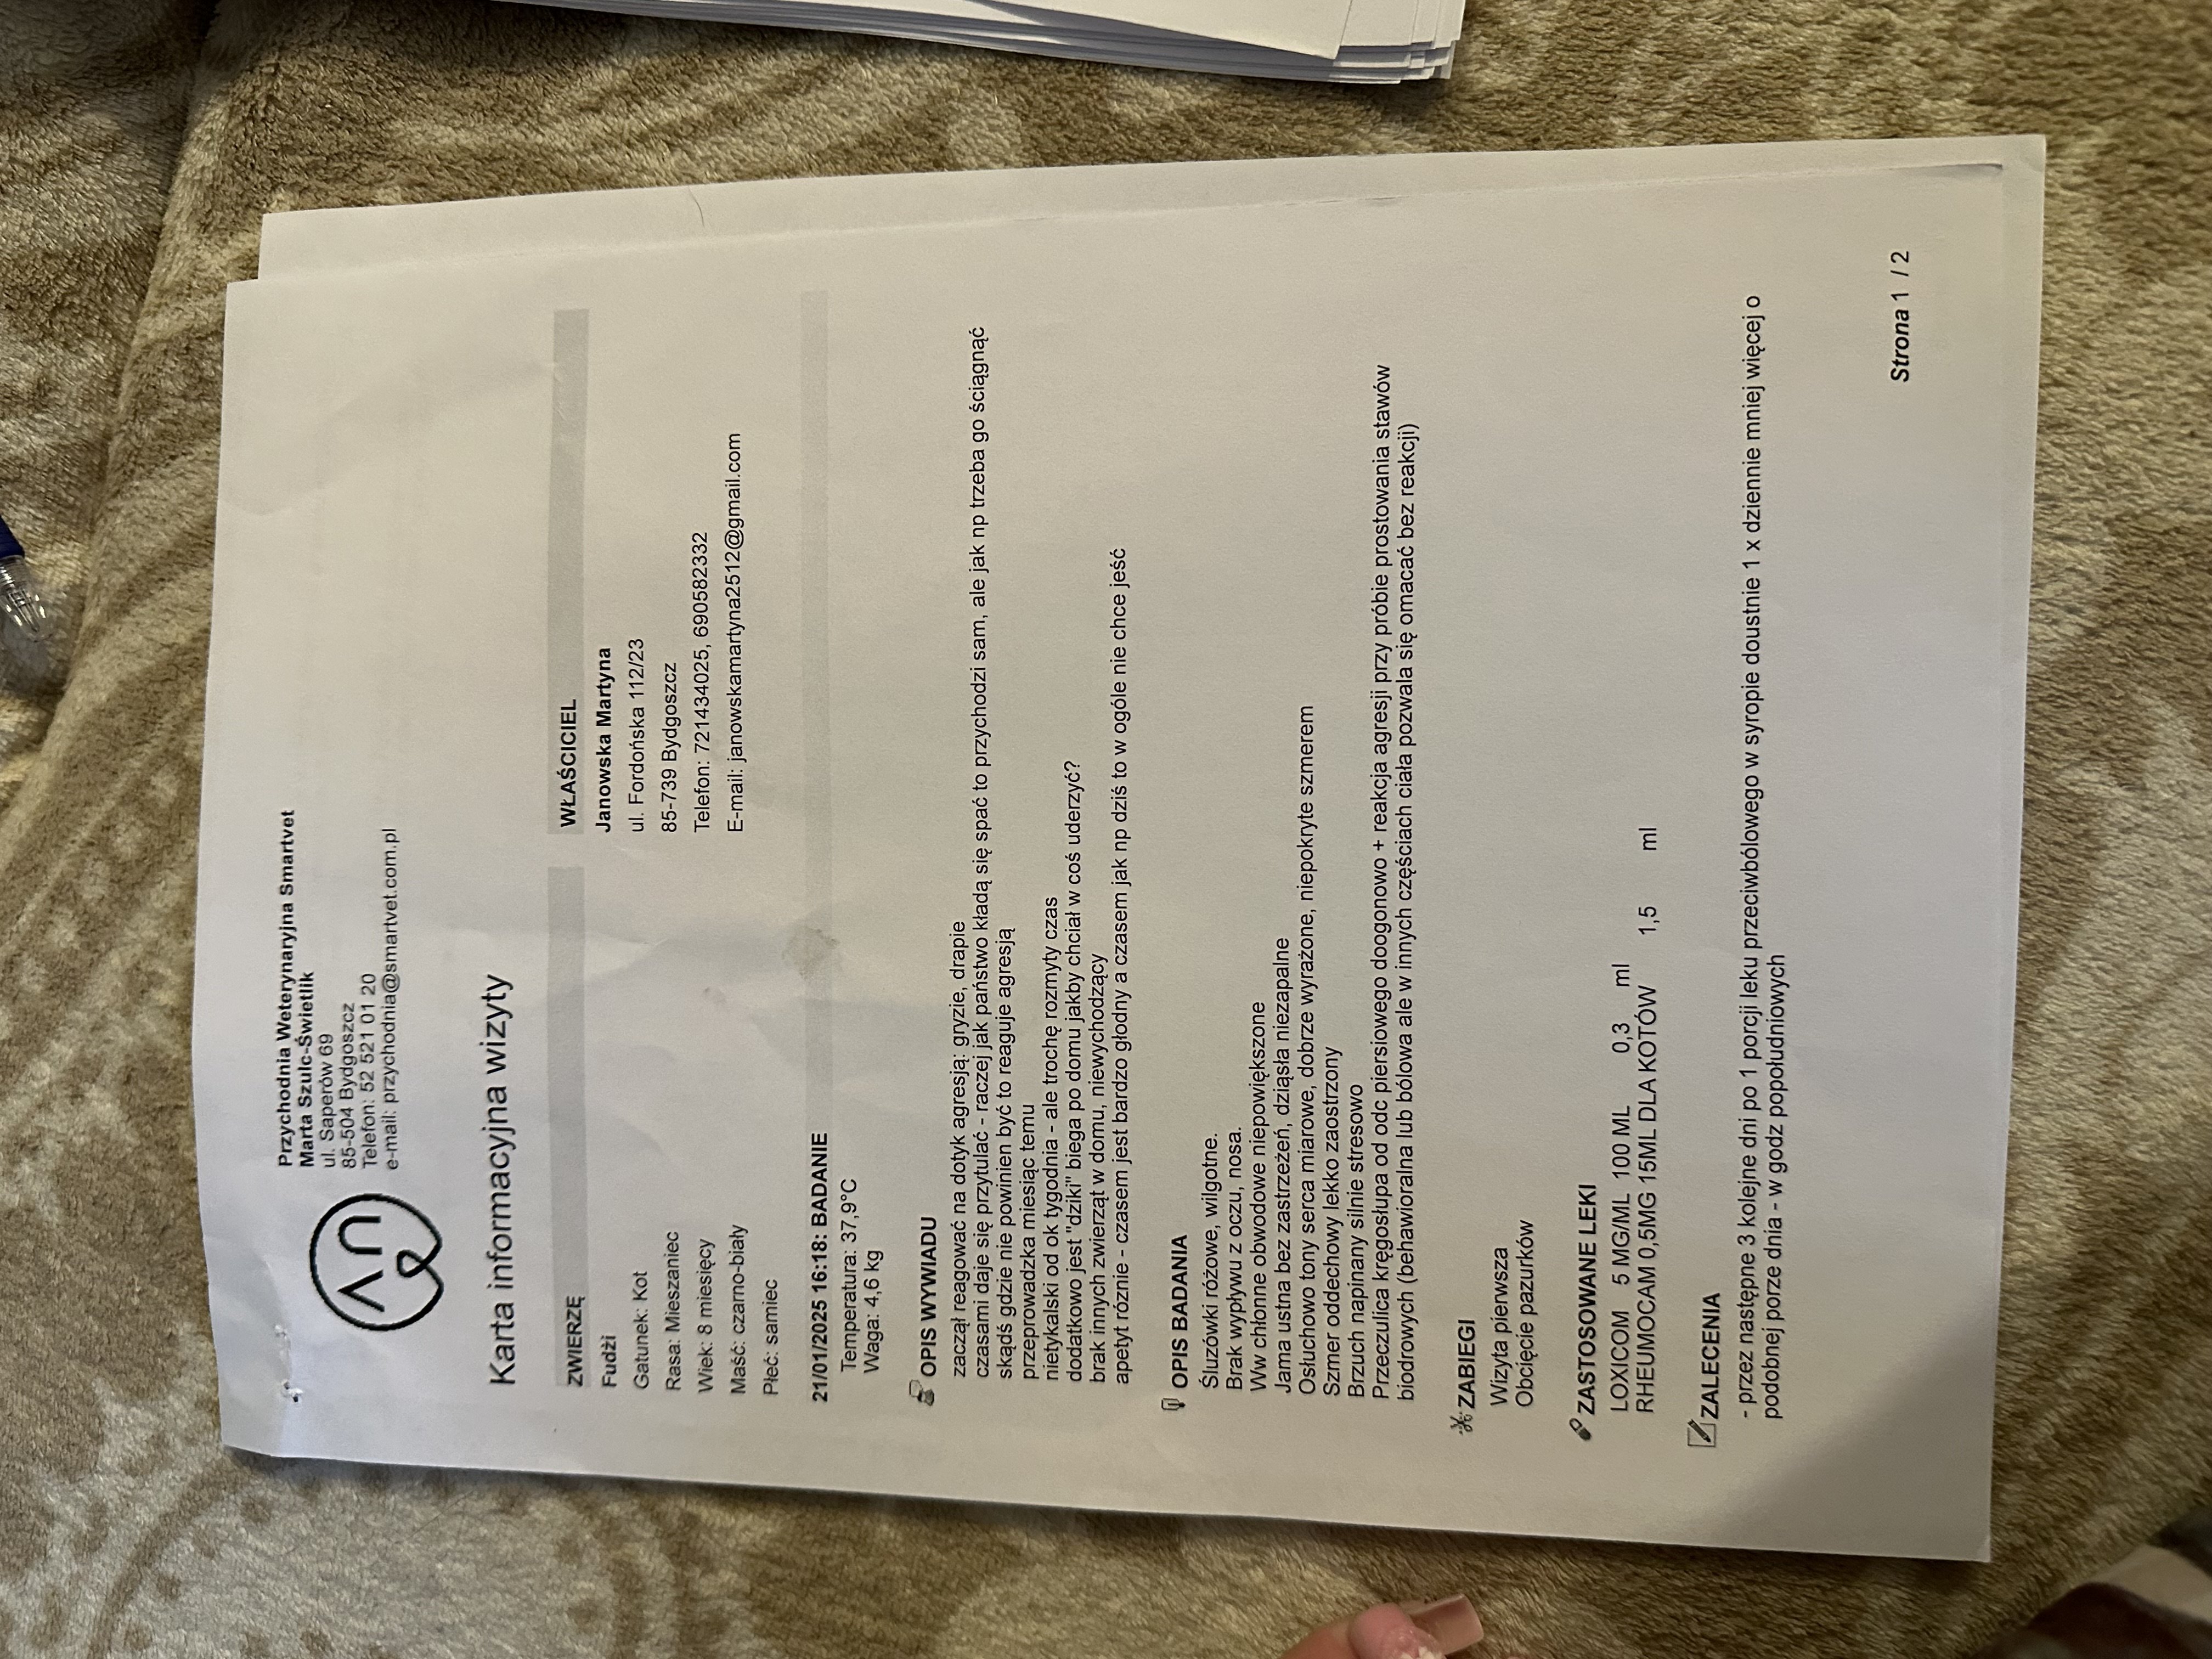

Cześć, zwracam się do Was z ogromną prośbą o wsparcie dla mojego kota Fudżiego. 🐈⬛ To młody, 9-miesięczny kocurek, który w krótkim czasie zaczął wykazywać niepokojące objawy – stał się agresywny, nie pozwalał się dotykać, atakował bez powodu, a jego apetyt bywał bardzo zmienny. Początkowo pojawiła się nadwrażliwość na dotyk w okolicach tylnej części ciała oraz nagłe ataki agresji.

Pierwsza wizyta u weterynarza wykazała możliwe problemy ortopedyczne – Fudżi wykazywał silny stres, miał napięty grzbiet, a próba wyprostowania jego stawów biodrowych wywoływała agresję, co mogło świadczyć o bólu. Wstępnie podano mu leki przeciwbólowe (Loxicom, Rheumocam) i zalecono dalszą diagnostykę.

Kolejna konsultacja miała miejsce w innej klinice, gdzie lekarze nadal podejrzewali problemy ortopedyczne, dlatego przeszedł szczegółowe badania, w tym RTG kręgosłupa i bioder i konsultacje specjalistyczną. Wdrożono leczenie Gabapentyną oraz Metacamem, aby zmniejszyć ból i uspokoić kota. Zalecono dalszą obserwację oraz ewentualne kolejne badania, jeśli objawy nie ustąpią.